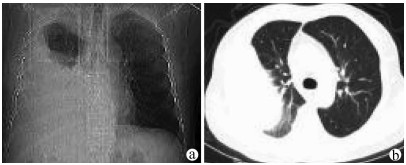

Alagille综合征1例报告

汤珊, 白丽, 宋文艳, 梁晨, 白洁, 郑素军

2021, 37(9): 2185-2187. DOI: 10.3969/j.issn.1001-5256.2021.09.036

摘要(964) HTML (503) PDF (2747KB)(59)

摘要: